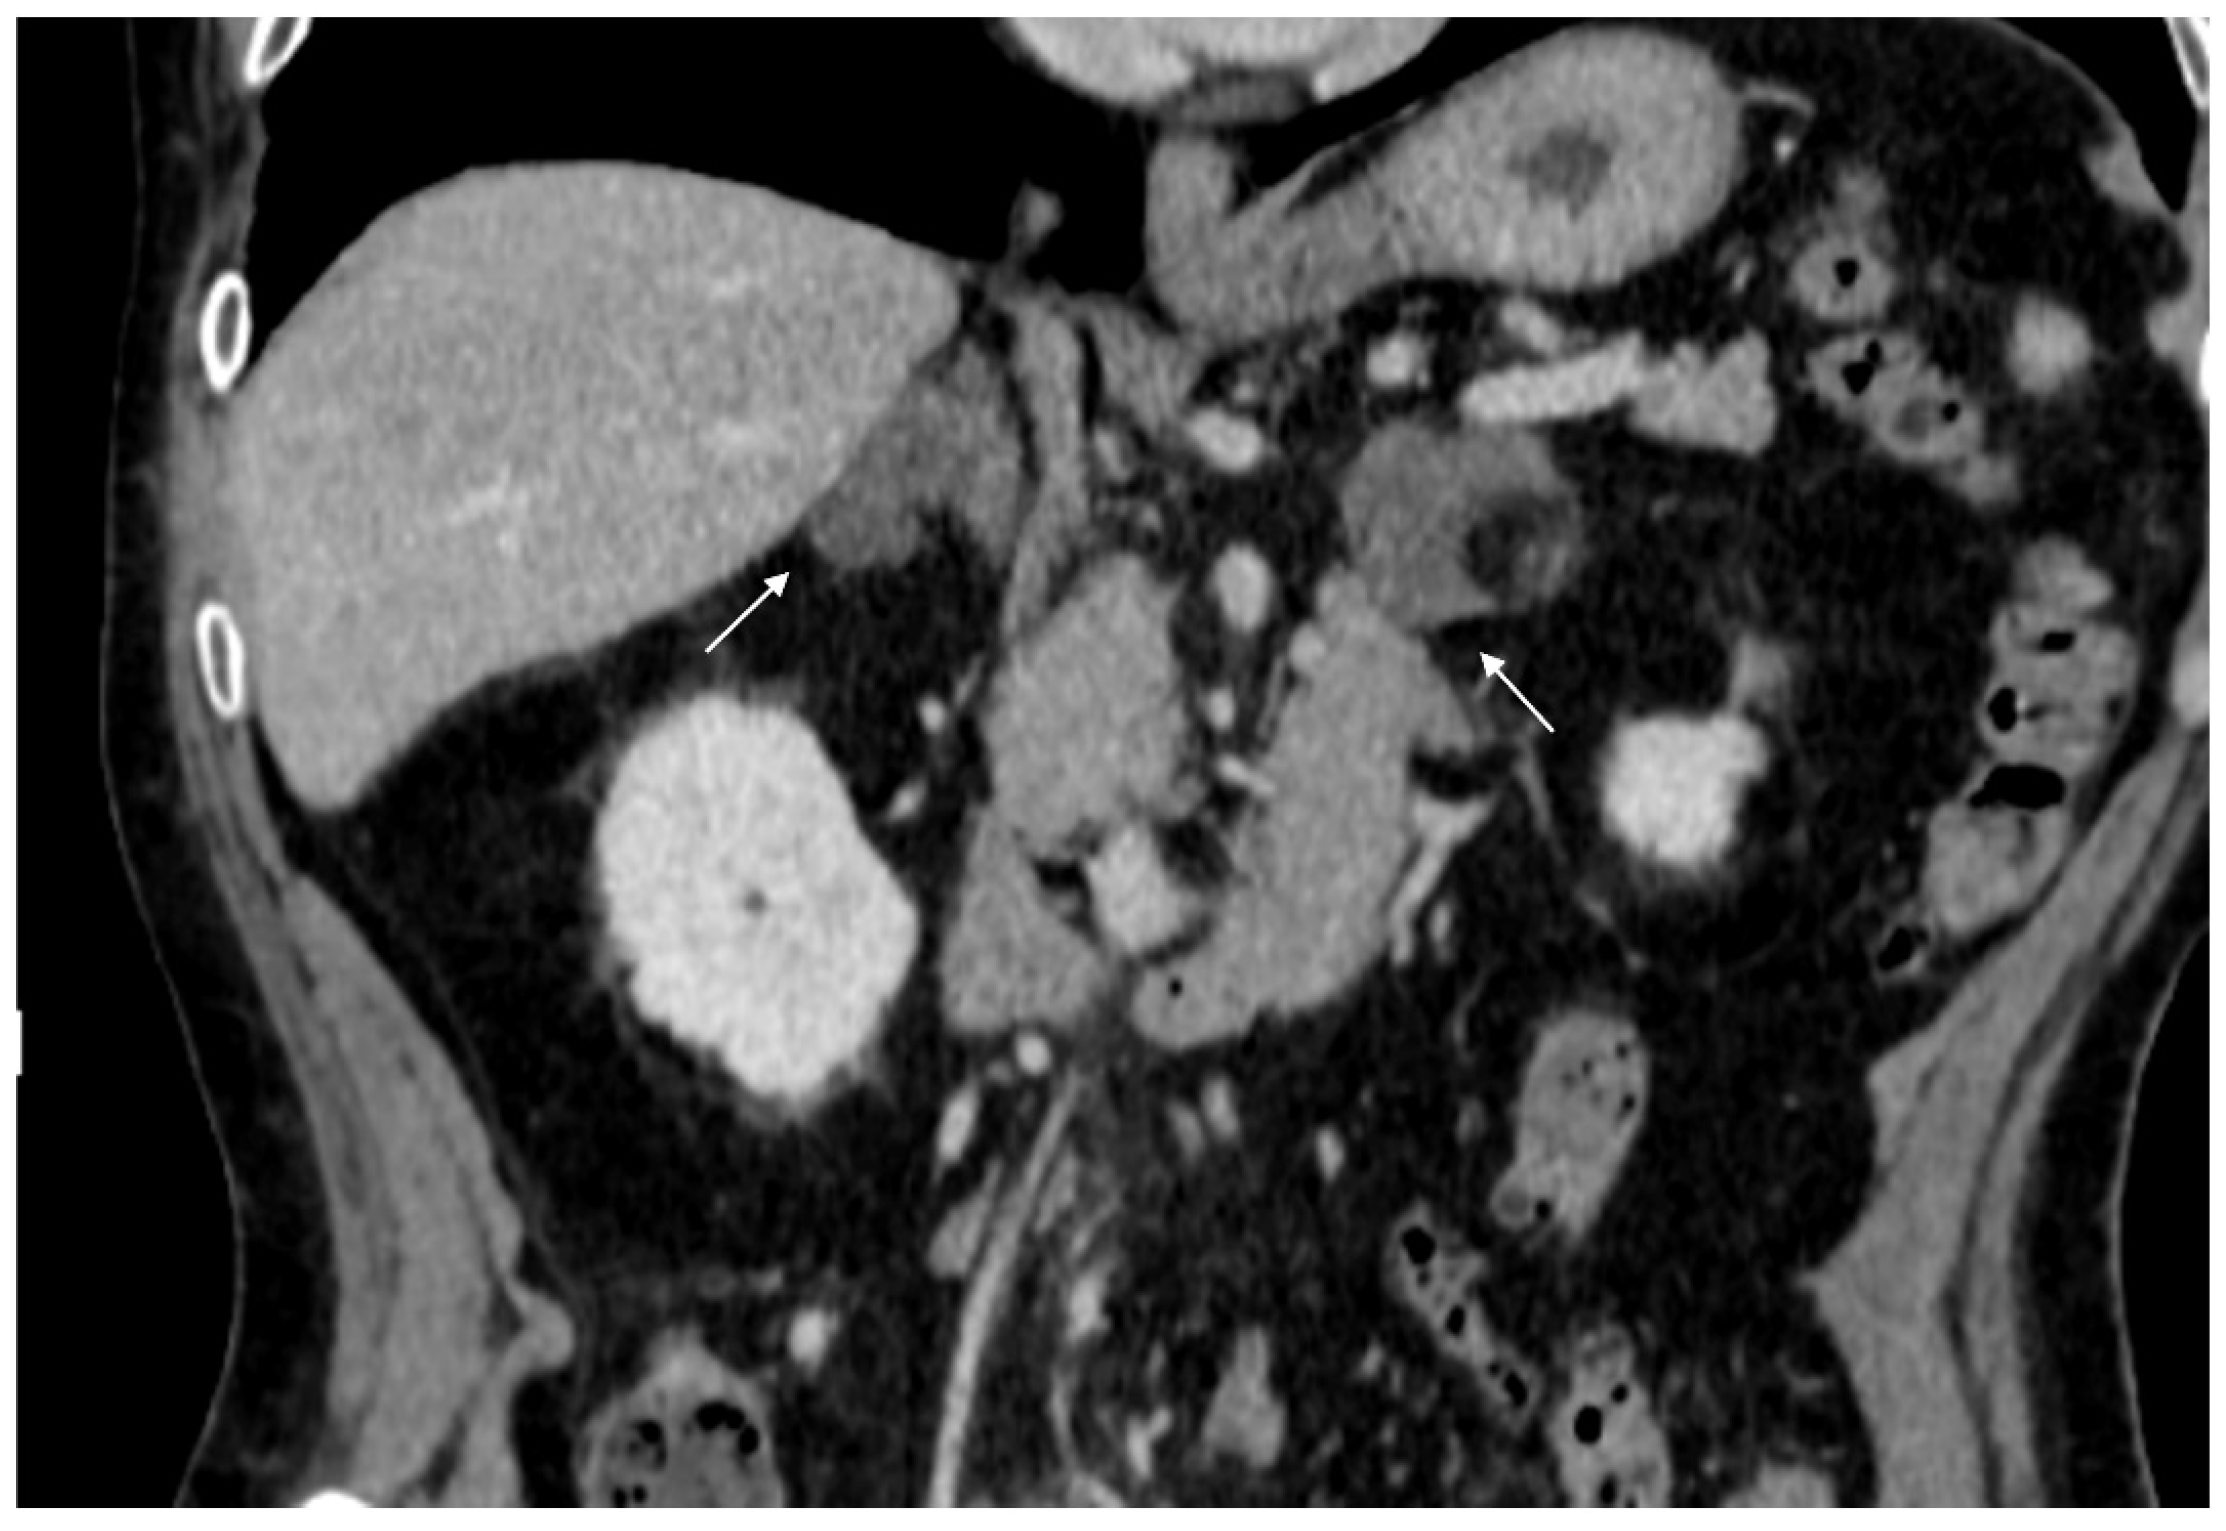

Figure 16.

(a) Axial and (b) coronal venous phases CT show an ACC of the left adrenal gland presenting as a large mass (arrow) of heterogeneous appearance with extensive neoplastic thrombosis of the ipsilateral renal vein.